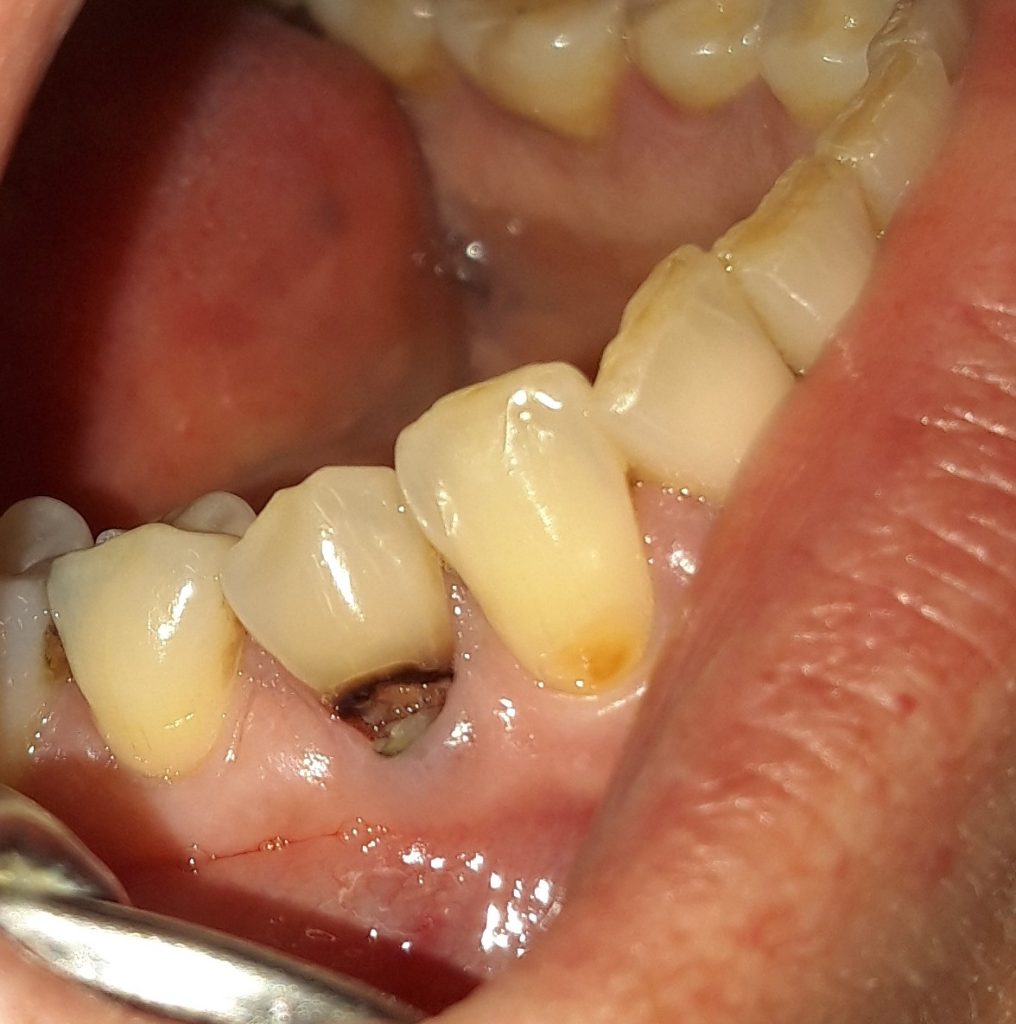

Η τερηδόνα προσβάλλει συνήθως τη μασητική επιφάνεια ενός δοντιού. Σε άλλες πάλι περιπτώσεις είναι δυνατόν να εμφανιστεί στον αυχένα δοντιού. Αρχικά εμφανίζεται σαν μία μικρή καφέ κηλίδα. Εφόσον ο ασθενής δεν επισκεφτεί άμεσα τον οδοντίατρο, είναι δυνατόν η τερηδόνα από τον αυχένα του δοντιού να προχωρήσει σε μεγαλύτερο βάθος και να φτάσει να προσβάλλει το νεύρο του δοντιού. Για το λόγο αυτό είναι σημαντικό ο ασθενής στην εμφάνιση μιας μικρής τρύπας / τερηδόνας να απευθύνεται άμεσα στον οδοντίατρο για την επίλυση οποιουδήποτε οδοντικού προβλήματος προκύπτει. Άλλωστε μία μικρή τερηδονική αλλοίωση αντιμετωπίζεται ευκολότερα και γρηγορότερα συγκριτικά με ένα δόντι που χρειάζεται απονεύρωση.

Στις περισσότερες περιπτώσεις μία τερηδόνα που εμφανίζεται στον αυχένα του δοντιού αποκαθίσταται με λευκό σφράγισμα δοντιού. Πρόκειται για μία απλή και καθόλου επίπονη διαδικασία.